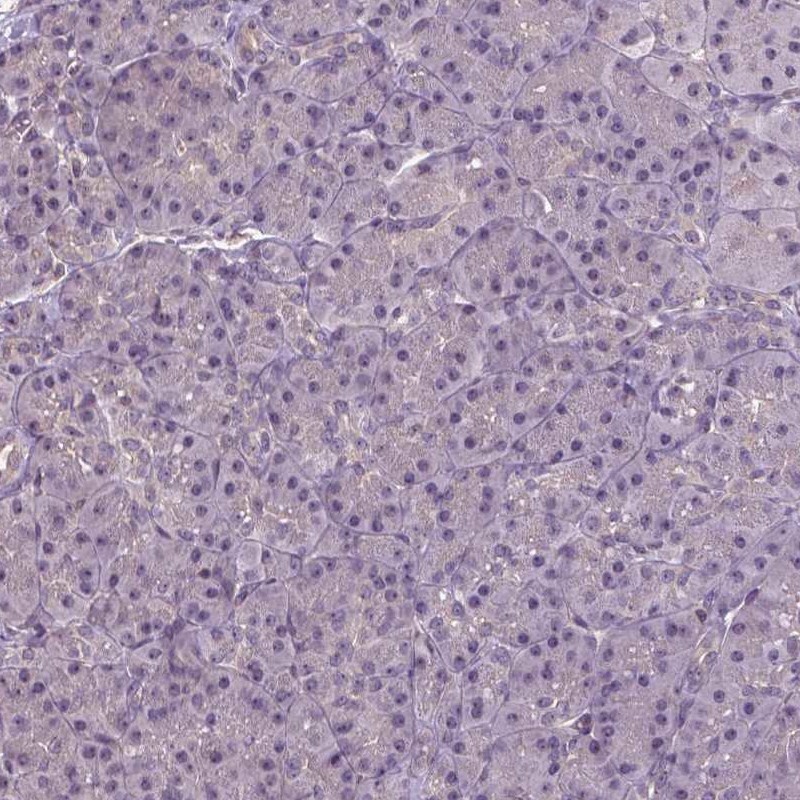

Immunohistochemistry analysis in human duodenum and pancreas tissues using Anti-ANXA13 antibody. Corresponding ANXA13 RNA-seq data are presented for the same tissues.